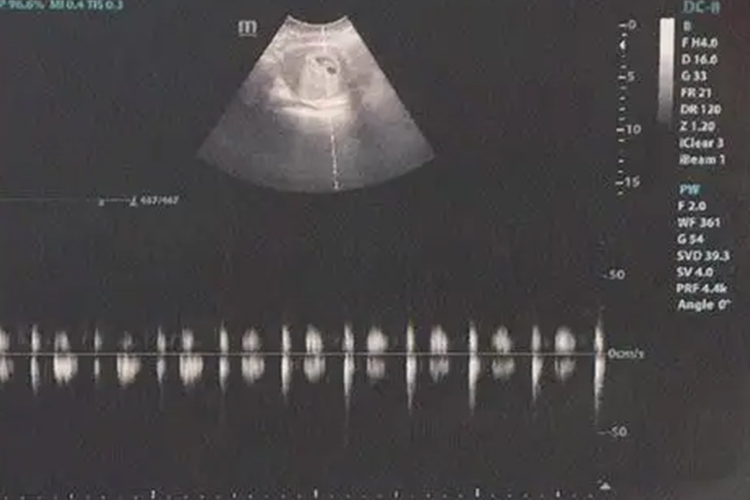

妊娠6周时,B超可见到胚芽和原始心管搏动。

怀孕早期B超检查的主要目的是确定宫内妊娠,排除异位妊娠、滋养细胞疾病、盆腔肿块等。若为多胎,可通过胚囊数目和形态判断绒毛膜性。停经35日时,宫腔内见到圆形或椭圆形妊娠囊;妊娠6周时,可见到胚芽和原始心管搏动,妊娠11-13周测量胎儿头臀长度能较准确地估计孕周,校正预产期。